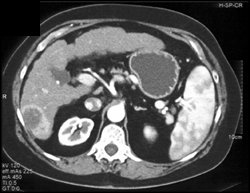

Dilated Ducts Left Lobe of Liver